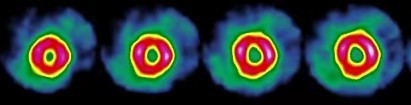

利用正常或有功能的心肌细胞选择性摄取某些核素或其标记化合物,应用γ相机或SPECT进行心肌平面或断层显像,可使正常或有功能的心肌显影,从而反映心肌的血流灌注,而坏死心肌及缺血心肌不显影或显影变淡。心肌对灌注显像剂的摄取决定于两个因素:局部心肌的血流量和心肌活性。心肌血流量多,心肌细胞活性正常,心肌摄取显像剂多,反之则摄取减少。由于心肌每个部位聚集放射性的多少与该部位冠状动脉灌注血流量呈正相关,可根据局部放射性的多少可以分析冠脉血流灌注及心肌细胞活性情况。通常自右前斜位45°至左后斜位45°,旋转180°或行360°采集,采集30-60个投影,利用特定的处理软件获得左心室心肌短轴、水平和垂直长轴断层图(如下图)。

心肌灌注显像可分为静息显像和负荷显像。前者是在安静状态下的心肌显像,而后者是在给予心脏一定“负荷”条件下的显像。负荷心肌灌注显像可以提高冠心病的检出率,其原理为正常冠脉有一定的储备供血能力,而狭窄的冠脉储备供血能力明显降低,在负荷试验时,正常冠状动脉供血区的心肌血流灌注能明显增加,而狭窄的冠状动脉供血区的心肌血流灌注增加不明显甚至不增加,从而导致病变区域心肌对显像剂的摄取绝对或相对减少,在心肌显像图上表现为放射性稀疏或缺损区。异常图像可表现为完全可逆性灌注缺损、不可逆性灌注缺损、混合性灌注缺损、花斑型异常、反向再分布。心肌梗死和心肌缺血分别表现为病灶处放射性缺损和放射性减低。同时心肌摄取和清除灌注显像剂受到心肌细胞活力和膜完整性的影响,感染性心肌炎因局部炎症造成心肌细胞的损伤、坏死从而减弱或失去摄取显像剂的能力,致使显像图像上呈现为放射性减低或(和)缺损。病毒性心肌炎是由病毒侵犯心脏所致局限性或弥漫性心肌炎性损伤,因病变心肌摄取显像剂的能力降低而表现为多发局限性或弥漫性放射性稀疏或缺损(如下图),典型图像呈花斑样改变。